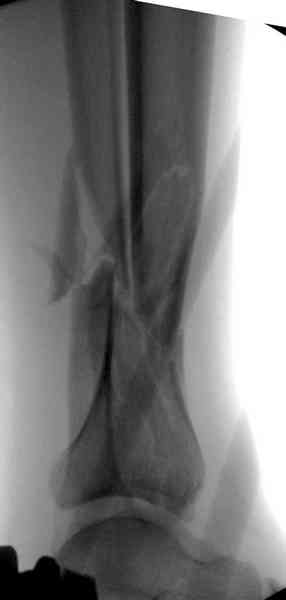

При высокоскоростных переломах редко можно встретить изолированную травму пилона, и в моей практике изолированные травмы большая редкость, поэтому, как дополнение к обсуждаемой теме, решил представить свежий, двухдневной давности случай.

Предыдущей сменой до 4:00 утра по поводу открытого перелома бедра, тибиал плато, пилон и надколенника сделана операция.

Пострадавшему 21 г., травма скоростная, после I&D с расширением раны, на бедре сделана операция ретроградным интрамедуллярным штифтом, остеосинтез с частичной резекцией надколенника и ушивание собственной связки.

КТ пилона имеем.